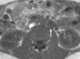

Para-aortic lymphadenopathy

Ovarian cancer is a cancer that forms in or on an ovary. It results in abnormal cells that have the ability to invade or spread to other parts of the body. [Source: Wikipedia ]